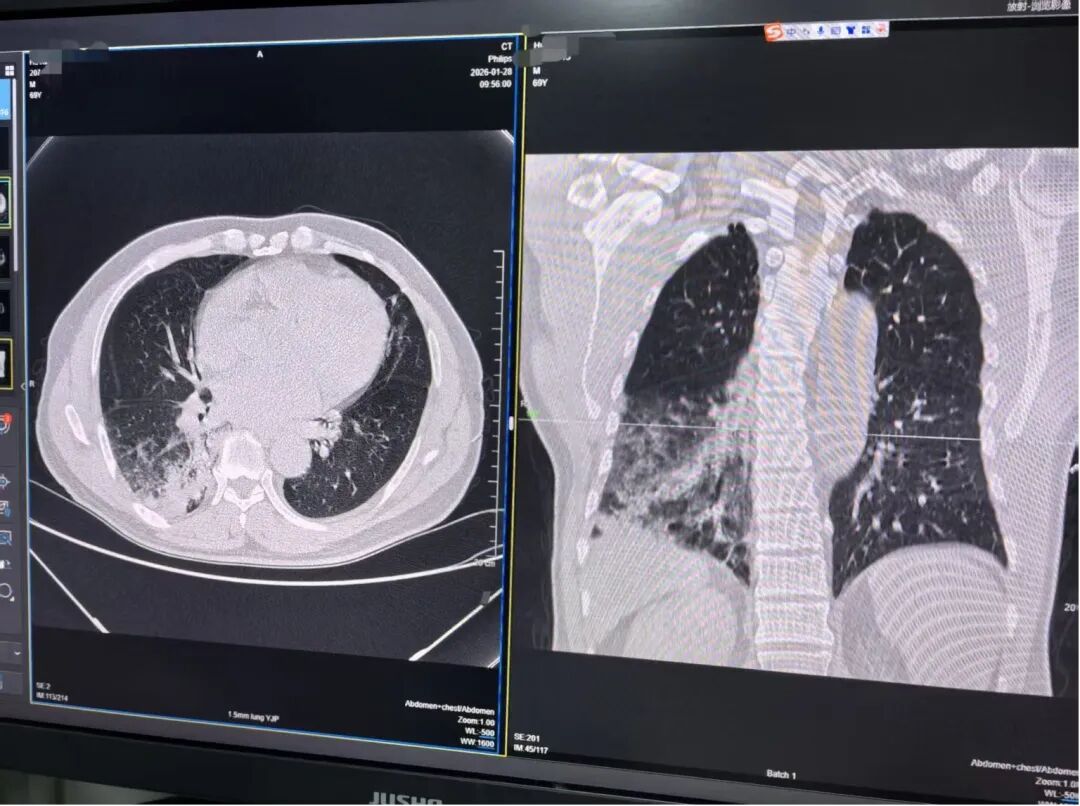

胡爷爷的肺部CT结果

据湖南中医药大学第一附属医院老年病科/全科医学科副主任医师陈亚介绍,胡爷爷入院当天体温高达39.8℃,连续用药后仍高热不退,因胡爷爷有家禽接触史,加上科室连续接诊了两例鹦鹉热,于是立即完善相关检查,最终经过诊断,胡爷爷确诊鹦鹉热衣原体感染。